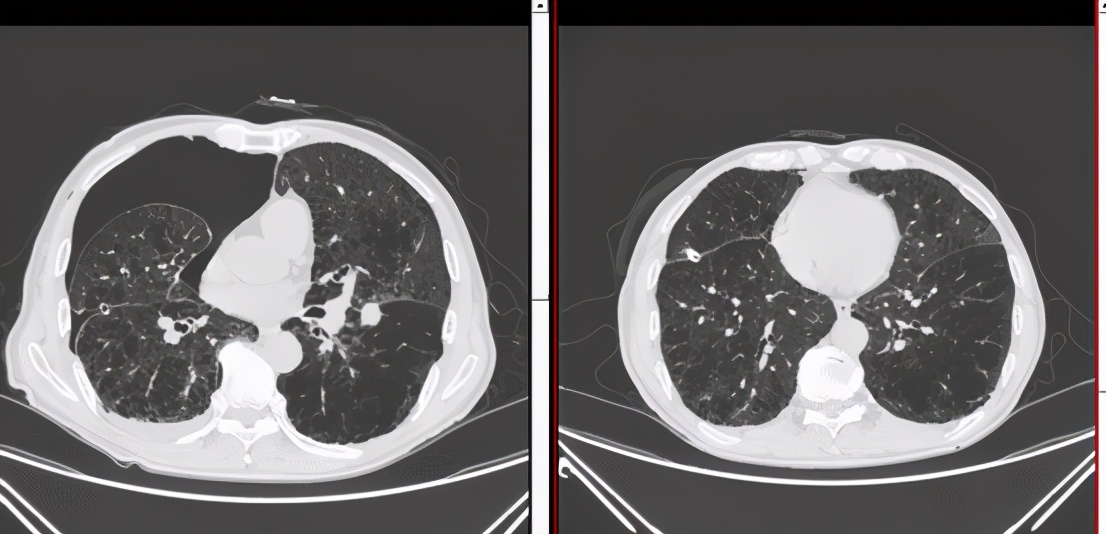

家属为病人办好住院手续后,祈福医院呼吸科主任接待了郭老先生,并且立即开始了会诊,通过胸部的CT造影后,大家发现郭老爷子的肺部真的已经到了病入膏肓的境地。

郭老爷子的双肺出现了严重肺气肿、肺大疱并发其他症状,而且郭老爷子的胸部引流管已经存在了三个月了,如此下去不但没有办法治好郭老先生的肺病,还会让他的生活质量严重下降。

医生很疑惑,气胸其实是一件不大的事情,而且引流管处理方法完全符合正常的处理方式,那么为什么一直好不了呢?

秉着认真负责的态度,医生开始仔细观察CT,经过深思熟虑,陈医生幡然醒悟,问题很有可能出现在引流管上!